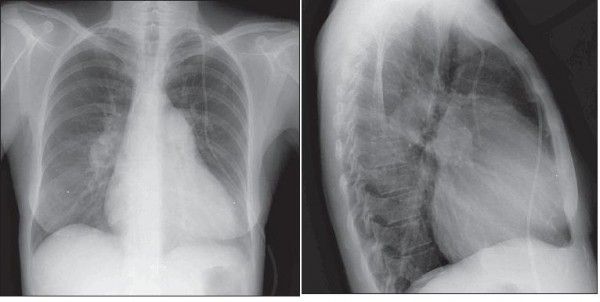

Cardiomegaly and prominent bilateral pulmonary arteries in the hilar areas can be seen in the posteroanterior chest radiograph from a patient with idiopathic pulmonary arterial hypertension. The lateral view also reveals enlarged pulmonary arteries and cardiomegaly without any evidence of congestive heart failure.